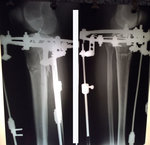

Ножки на сращении

nogi-01.jpg

nogi.jpg